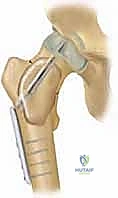

ثالثاً: العلاج الجراحي المتخصص (الكشط والتطعيم العظمي)

يُعد التدخل الجراحي هو المعيار الذهبي والعلاج الحاسم في الحالات التالية:

1. فشل العلاج بالحقن المتكرر.

2. الأكياس الكبيرة جداً التي تهدد بكسر محتم.

3. حدوث كسر مرضي بالفعل يحتاج إلى تثبيت.

4. معظم حالات كيس العظم المتمدد (ABC) نظراً لطبيعتها العدوانية واحتمالية الانتكاس العالية.

التخطيط الجراحي المسبق هو مفتاح النجاح. يقوم الدكتور هطيف بتحديد مكان الشق الجراحي وحجم النافذة العظمية المطلوبة للوصول إلى الكيس بأمان تام.

خطوة بخطوة: كيف يُجري الأستاذ الدكتور محمد هطيف جراحة الكشط والتطعيم العظمي؟

الجراحة في عيادة ومستشفيات الأستاذ الدكتور محمد هطيف في صنعاء ليست مجرد إجراء روتيني، بل هي عمل فني يجمع بين الدقة المتناهية واستخدام أحدث التقنيات الطبية